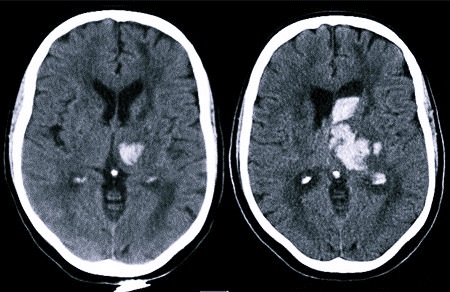

В ходе диагностического обследования могут использоваться инструментальные и лабораторные методы:

- компьютерная и магнитно-резонансная томография – КТ и МРТ;

При геморрагическом инсульте возможно образование гематомы, которую придется удалять с помощью хирургической операции. Выявить ее точное расположение и установить объем скопившейся крови поможет визуализация посредством МРТ-метода.

Если диагностирован инсульт с кровоизлиянием в мозг, последствия будут зависеть от объема крови, попавшей в мозговое пространство, и локализации сформировавшейся гематомы. Именно эти параметры имеют определяющее значение в плане быстроты и полноты восстановления утраченных функций.